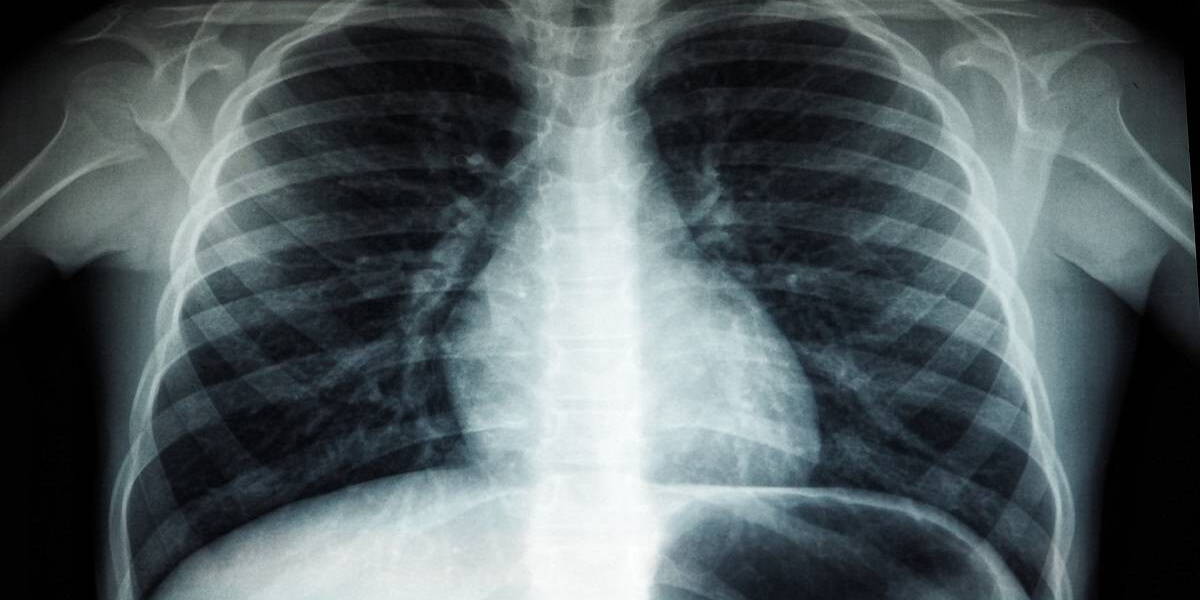

Door artsen gebruik te laten maken van zogenoemde C-bogen, die eruitzien als een letter C, kunnen artsen röntgenbeelden maken tijdens een behandeling, zodat zij goed kunnen zien wat ze in het lichaam doen. Dit is mogelijk door röntgenstraling en nucleaire beeldvorming samen te voegen.

Bij behandelingen van sommige soorten kanker, maar ook bijvoorbeeld bij cardiologische ingrepen, zou het nuttig kunnen zijn om naast beeldvorming met röntgenstraling tegelijk ook nucleaire beeldvorming te realiseren. Daarbij wordt gebruik gemaakt van oplichtende radioactieve stoffen in het lichaam. Nucleaire beeldvorming is vooral geschikt om het functioneren van organen in beeld te brengen, zoals de bloedstroom door het hart of de stofwisseling in de hartspier.

Klinisch fysici van de afdeling Radiologie en Nucleaire Geneeskunde van het UMC Utrecht hebben de afgelopen jaren een hybride C-boog ontwikkeld waarmee tegelijkertijd röntgen- en nucleaire beelden gemaakt kunnen worden.

“Tot op dit moment was het niet mogelijk röntgenstraling en nucleaire beeldvorming samen te voegen voor gebruik in een behandelkamer,” zegt Hugo de Jong, klinisch fysicus in het UMC Utrecht. “De twee technieken veilig en effectief combineren bleek mogelijk met een gepatenteerde dubbellaags detector. Eerder hebben we deze innovatie al succesvol klinisch getest bij een specifieke kankerbehandeling: radio-embolisatie van de lever.”